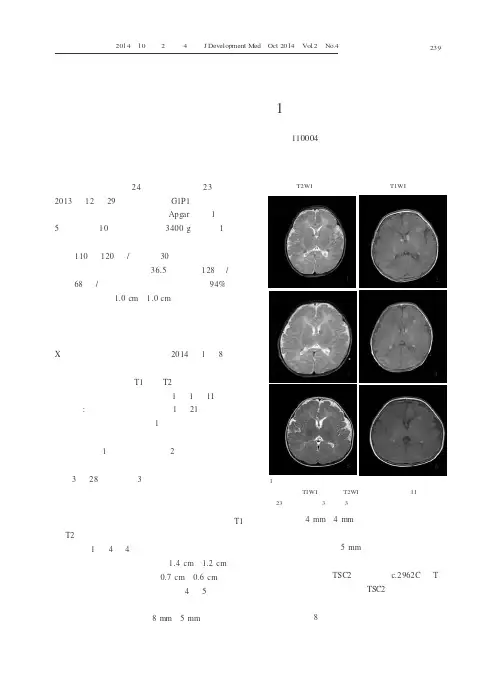

2014年1月8日头磁共振检查:双额顶叶、半卵圆区、侧脑室旁及基底节区多发点片状短T1、短T2信号,弥散加权成像提示部分病灶略高信号(图1)。

1月11日动态脑电图:左额、中央区棘波灶。

1月21日复查头磁共振较前无明显改变(图1)。

复查头磁共振提示双侧半卵圆中心、侧脑室旁、基底节区、额顶颞枕叶多发斑片模糊样短T1短T2信号影,尤其以脑室旁、皮层与白质交界处明显(图1)。